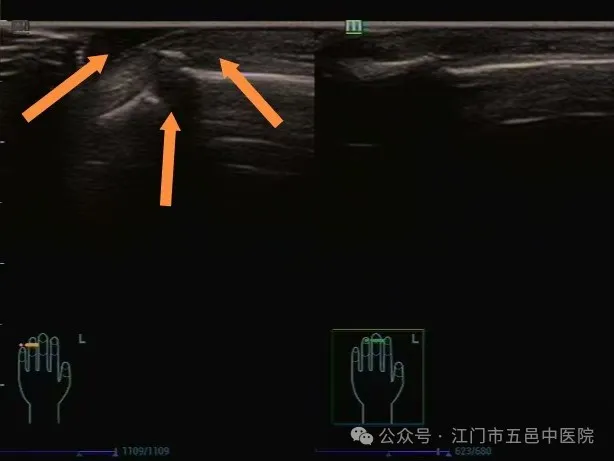

❖打篮球导致的闭合性指伸肌腱断裂

▲指伸肌腱连续性中断并伴远节指骨微小撕脱性骨折